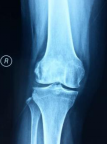

膝关节骨关节炎病案一例

DR:关节间隙变窄、关节缘骨赘形成

2X线片(站立或负重位)示关节间隙变窄、软骨下骨硬化 和(或) 囊性变、关节缘骨赘形成